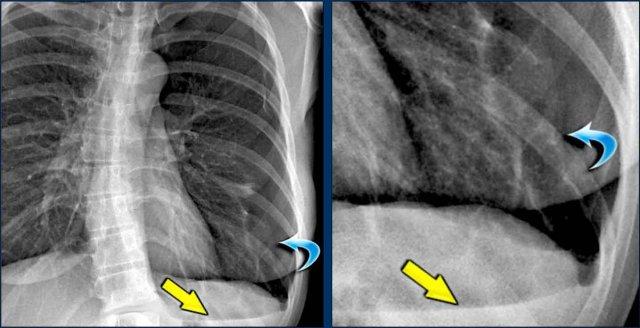

Dịch chuyển đường azygô-thực quản (1) – Thoát vị hoành

Thoát vị hoành (đầu mũi tên) là nguyên nhân phổ biến nhất gây dịch chuyển đường azygô-thực quản quan sát thấy trên phim tư thế thẳng (PA).

Lưu ý hình ảnh khí trong túi thoát vị trên phim tư thế nghiêng (mũi tên đen).